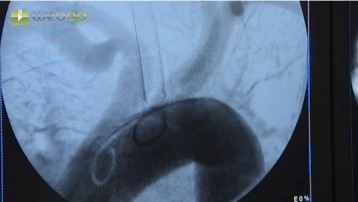

Puncione a artéria femoral direita pela técnica de Seldinger na virilha e introduza cuidadosamente o fio-guia. Remova a cânula de punção e introduza uma bainha de 6F ou 7F sob orientação fluoroscópica. Remova o fio-guia e verifique o fluxo de retorno pulsátil e, em seguida, administre localmente 5000 UI de solução salina de heparina. Sob orientação fluoroscópica, avance um fio-guia longo Terumo® através do eixo ilíaco direito para a aorta.